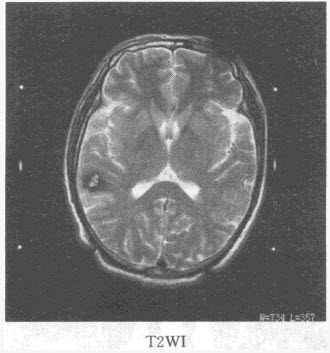

患者,女,36岁,抽搐半年,近10余天头痛加重,MRI检查如图,最可能的诊断是()

A:胶质瘤

B:脑膜瘤

C:动静脉畸形

D:海绵状血管瘤

E:蛛网膜囊肿